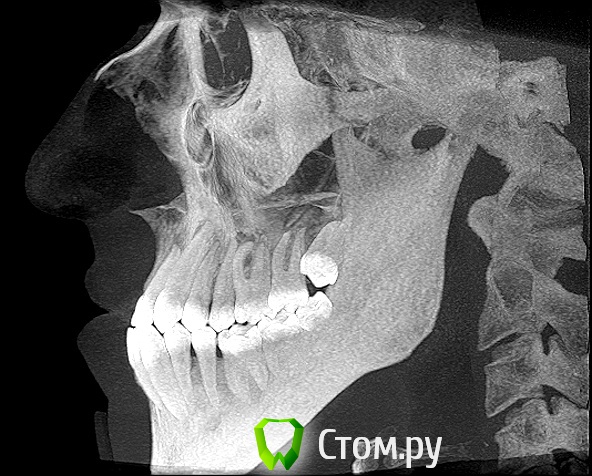

Здравствуйте! Мне 27 лет.  Очень вас прошу дать свою оценку моей ситуации. У меня сложная ситуация, я уже обошел многие ортодонтические кабинеты своего города и все говорят разное. У меня мезальный прикус, но своим профилем я доволен, я всем доволен, кроме того что у меня неправильный прикус (верхние резцы заходили за нижние и были вогнуты вовнутрь) и кривые зубки.Сейчас по рекомендации одного ортодонта ношу капу чтобы верхние резцы перепрыгнули, но теперь и это занятие меня сильно беспокоит, хотя ношу всего месяц и уже попадает зуб на зуб. Главный мой вопрос таков: "Возможно ли в моей ситуации исправить прикус без операции?" Спасибо за ответы!